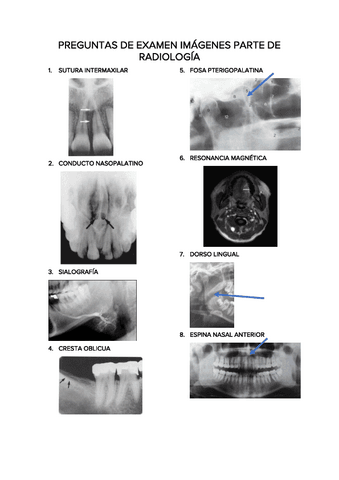

PREGUNTAS-DE-EXAMEN-IMAGENES-PARTE-DE-RADIOLOGIA.pdf

Exámenes - PREGUNTAS-DE-EXAMEN-IMAGENES-PARTE-DE-RADIOLOGIA.pdf